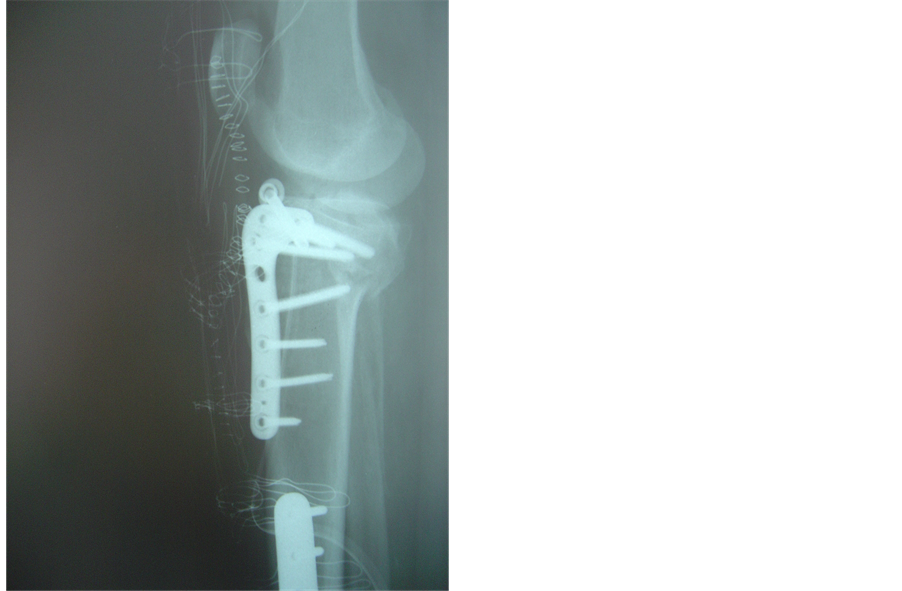

In three of our cases a hybrid fixator could not be used because of previous tibial shaft fractures that had been treated with open reduction and internal fixation―the presence of metal ware forbidding application of peripheral pins. In these cases, we chose to combine canulated screws with an anatomic lateral plate. Here, the canulated screws were applied open, through a lateral incision, but extremely close to the articular surface to allow correct positioning of the anatomic locking plate. The knee was once more not opened and the plate applied to unite the condyles to the shaft. Careful correction of varus-valgus malalignement and accurate canulated screw positioning were always checked with the II (Figures 3(a)-3(d)).

Figure 3. (a), (b): Schatzker VI fracture. Pre operative X-rays AP and Lateral; (c), (d): The fracture was treated with combination of canulated screw and anatomic locking plate because of presence of previous metal ware. Post-operative X-rays AP and lateral.